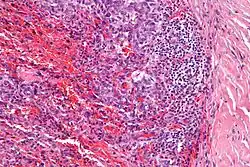

| Micrograph showing an angiomatoid fibrous histiocytoma. H&E stain. |

It is characterized by cystic blood-filled spaces and composed of histiocyte-like cells. A lymphocytic cuff is common. It often simulates a vascular lesion, and was initially described as doing this.[1]